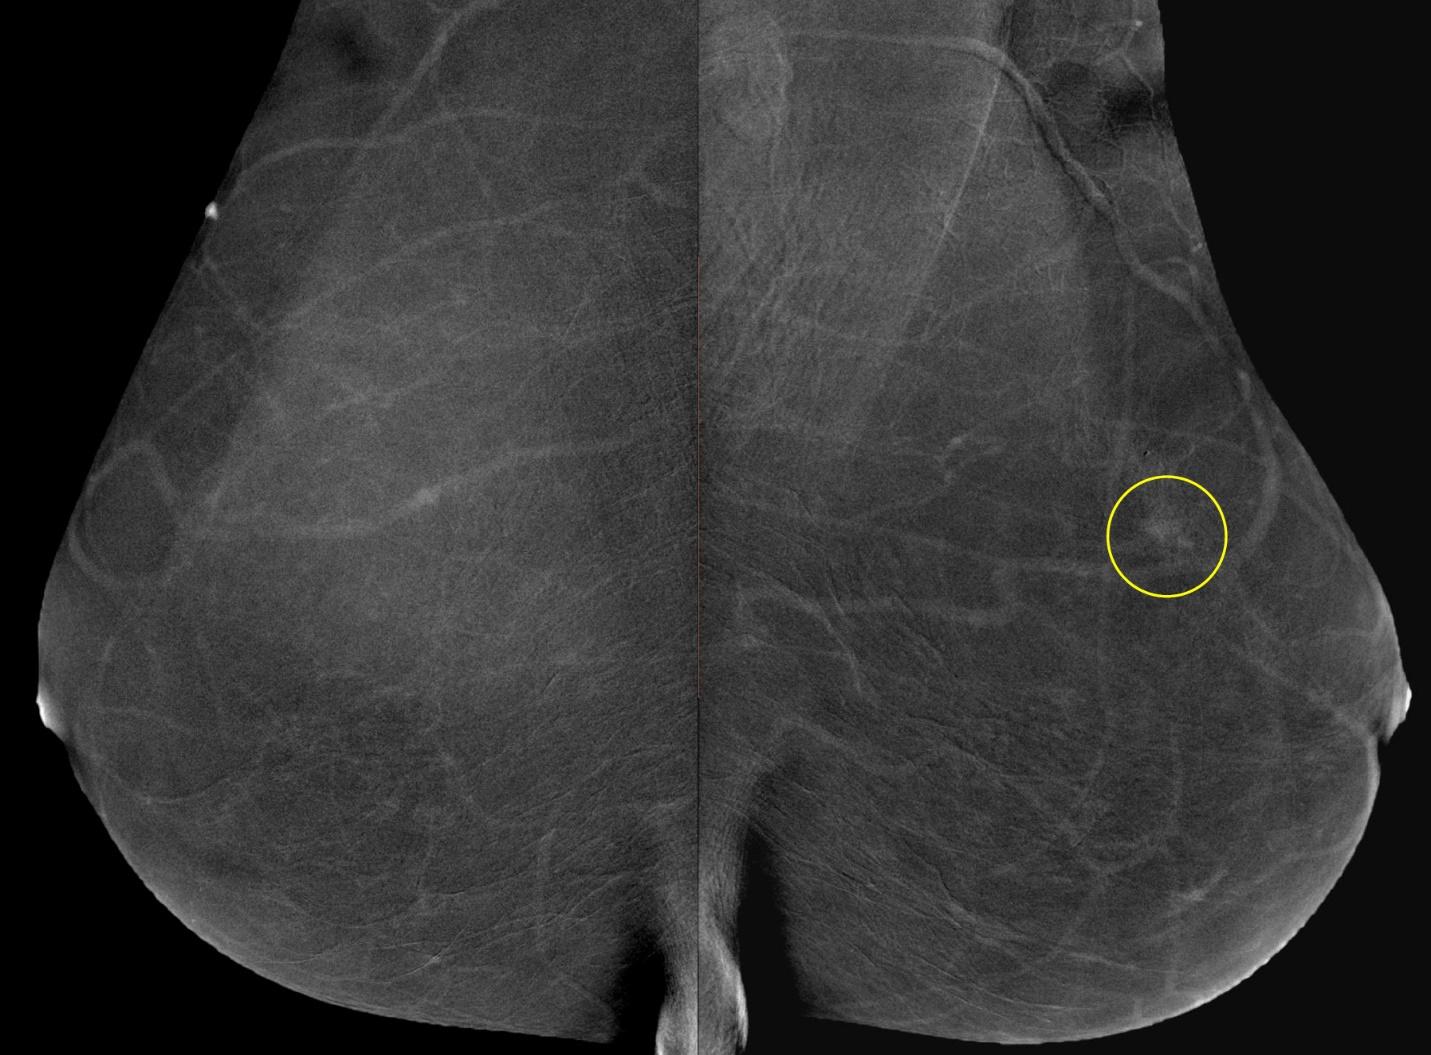

Пример сравнения классической маммограммы и томосинтезного среза

FFDM (2D) / BTM (3D)

Цифровой томосинтез, или 3D маммография, часто используется вместе с классической 2D маммографией для обследования плотных молочных желез или в качестве дополнительного метода при обнаружении патологий. Основным показанием для выполнения 3D маммографии является высокая плотность молочных желез (ACR C и D). В таких случаях может быть проведена маммография как в 2D, так и в 3D режимах в качестве основного метода обследования для пациентов старше 40 лет. В редких случаях томосинтез может быть использован после маммографии у женщин с низкой плотностью молочных желез для дополнительной диагностики, например, при подозрении на опухоль в молочной железе.

Сравнение томосинтезных срезов, сделанных на разных маммографических аппаратах

Клинические примеры применения CESM